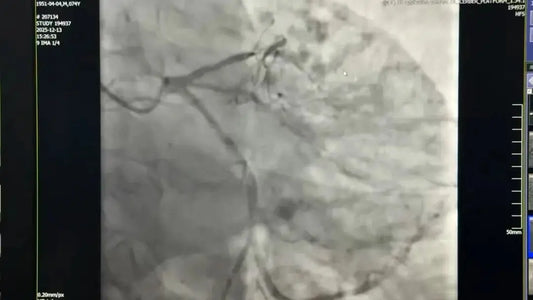

Fu Wai Hospital Uses Atherectomy and Stenting to Open CTO with Severe Calcification in 74-Year-Old Patient

Dr. Yang Honghui's team at Fu Wai Hospital successfully performed high-difficulty Rotational Atherectomy (RA) + precise Stent Implantation for a 74-year-old patient with Chronic Total Occlusion (CTO) and severe calcification....

Fu Wai Hospital Treats 85-Year-Old Patient with Complex Left Main Calcification Under ECMO Support

A multidisciplinary team (Emergency, CCU, Pulmonary, ECC) at Fu Wai Hospital successfully performed Rotational Atherectomy + Drug-Coated Balloon implantation under ECMO life support for an 85-year-old Acute Coronary Syndrome patient...